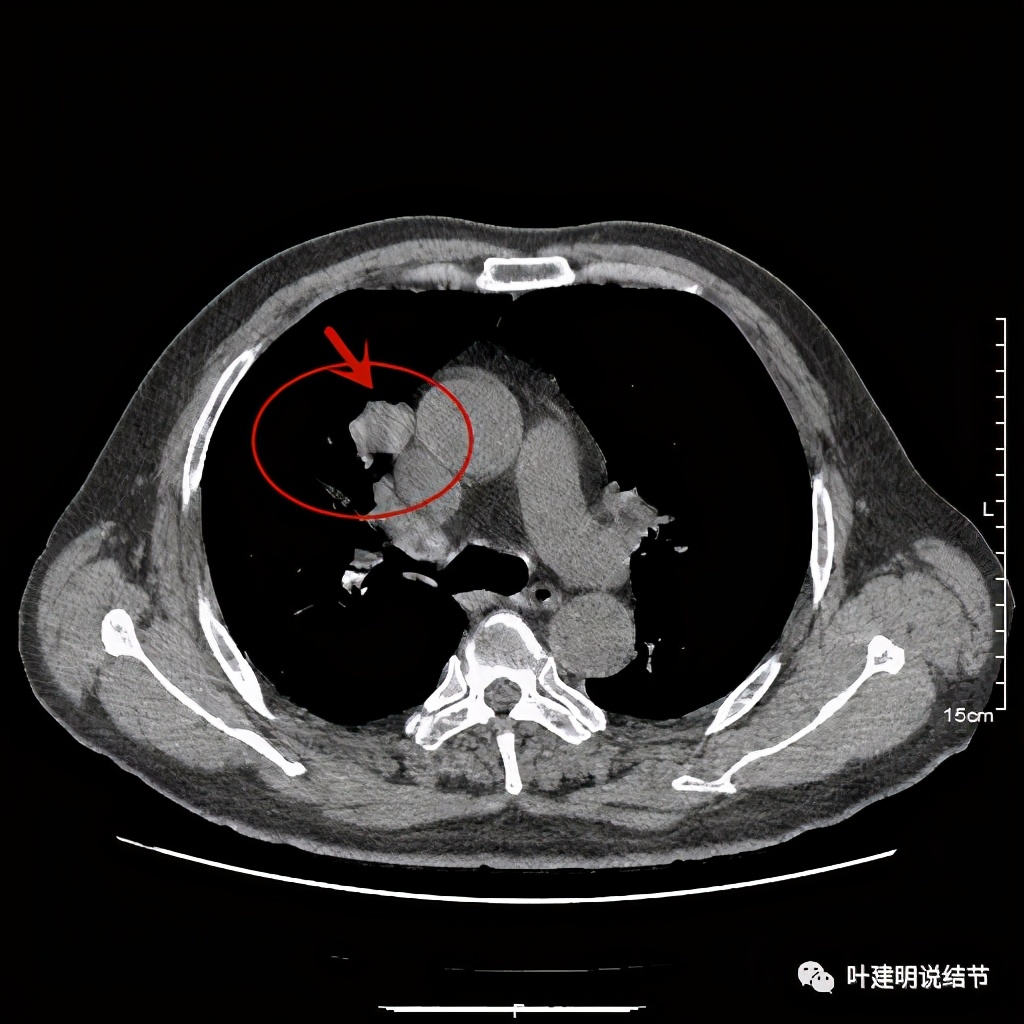

上图示病灶边缘过于光滑(绿色);局部有点状钙化(蓝色)

上图示病灶边缘过于光滑(绿色);血管贴边(桔色);

上图示病灶边缘过于光滑(绿色);血管贴边走行(桔色)

以上几图也示病灶边缘过光(绿色);血管贴边,感觉没受侵犯(桔色)

事前来看,达2.4厘米的不均质实性肿块,增强有轻度不均匀强化,血管贴边走行,支气管疑有截断,恶性不能除外,而且可能性较大。但现在经过手术已已经证实是错构瘤的情况下,我们回头来看,其实有许多不符合恶性的地方:

1、病灶的每个层面,边缘都过于光滑了。肺癌一般到这个大小总要有棘突、分叶、毛刺、牵拉周围胸膜等边缘异常的征象;

2、肿瘤大于2厘米以上,又紧贴血管,多有血管走行异常、受侵或血管进入等征象;

其实我们发现,包括今天这例,只要是错构瘤,“边缘非常光滑”是每一像都具备的!虽然有的似有支气管截断、有的似有血管征、有的似有分叶,但总的只要是边缘非常光滑的实性占位,就要想到错构瘤的可能,若有点状钙化密度,更是强烈要考虑。错构瘤如何靠近胸膜,其实可以切开一点肺实质,挤一下,肿瘤就会滚出来。